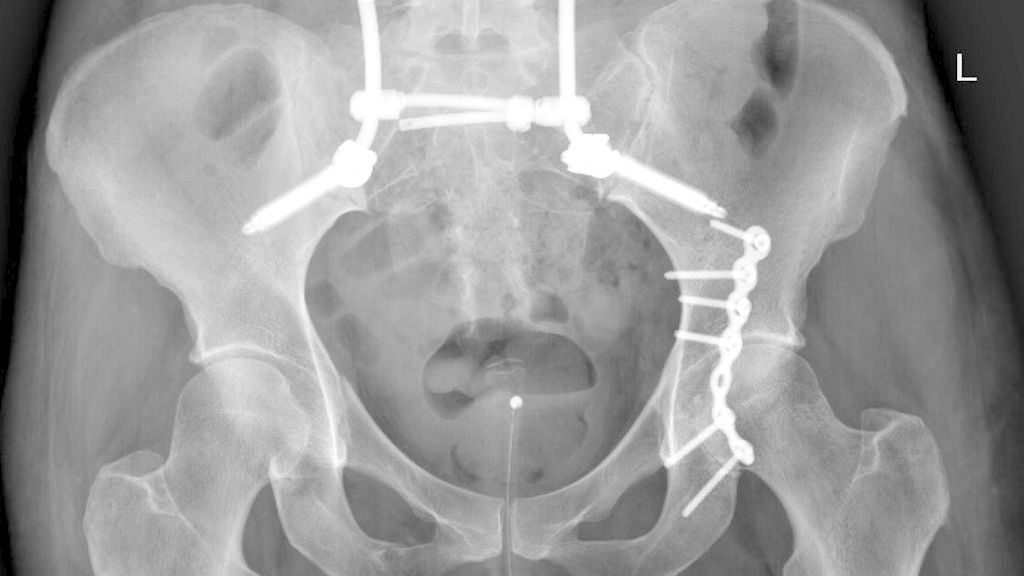

Die lumbopelvine Stabilisierung bietet als etabliertes Verfahren eine hohe biomechanische Stabilität. In diesem Artikel werden anhand der aktuellen Literatur und Empfehlungen die Indikationen, Vor- und Nachteile der lumbopelvinen Stabilisierung sowie die Abwägung mit alternativen Techniken bei Sakrumfrakturen behandelt.

Um die Indikationen der lumbopelvinen Stabilisierung (LPS) zu identifizieren, muss man sich mit den Arten der Sakrumfraktur auseinandersetzen. Die gängigste Klassifikation nach Denis unterscheidet nach der Lokalisation von lateral nach zentral die Denis-I-Fraktur im Bereich der Massa lateralis, Denis II mit Beteiligung der Foramina und Denis III mit zentralen Frakturausläufern. Diese Klassifikation ist hilfreich für die schnelle und einfache Beschreibung von Sakrumfrakturen und ist in erster Linie nützlich für die Abschätzung von Komplikationen. Denn die Häufigkeit neurologischer Ausfälle nimmt von Denis I nach III aufgrund der anatomischen Verläufe der Nervenwurzeln zu. Auch für Therapieentscheidungen lässt sie sich anwenden, da die Notwendigkeit einer Operation von Denis I nach III zunimmt. Über die Wahl der Operationstechnik gibt die Denis-Klassifikation jedoch keine Aufschlüsse.